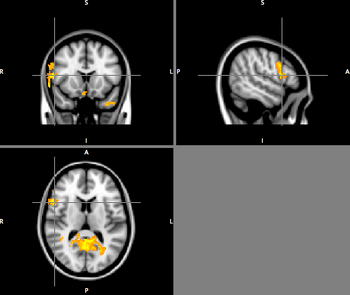

MDD > CTL for Accept Task: Regions of Increased Activation in the MDD Group

On the accept task (relative to baseline), significantly higher activation is observed in the MDD group relative to the control group in the inferior frontal gyrus, subgenual prefrontal cortex, thalamus, precuneus, and amygdala.